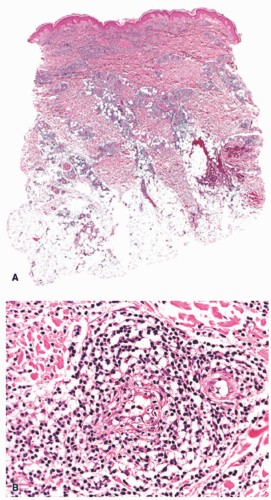

EI is histologically identical to nodular vasculitis. Because mycobacteria is not consistently identified in cases of EI, and because numerous inflammatory and other triggers are known to result in the clinical and histologic features of nodular vasculitis, this distinction in nomenclature between the two entities has fallen out of favor within dermatopathology as well, with many authors preferring a unified description.10 EI-nodular vasculitis is characterized histologically by a primarily lobular panniculitis, with lymphohistiocytic granuloma formation and variable necrosis (Figure 5-3A). Vasculitis is the most reliable finding and may present as a necrotizing form in early lesions (Figure 5-3B).11 Careful search for mycobacterial organisms should be done, using special stains (AFB [acid-fast bacilli], FITE) or immunohistochemistry for tuberculosis.